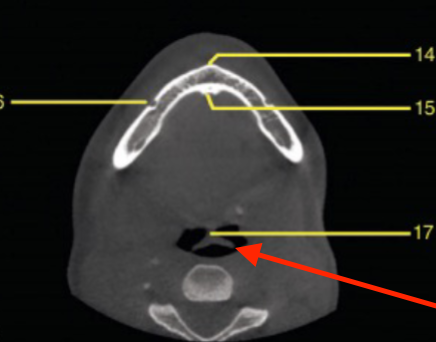

axial

what plane is this

level of maxilla (above maxillary teeth)

at what level is this

mandibular condyle

what structure is this

coronoid process

apical of roots

genial tubercule

identify structure